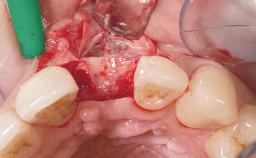

Immediate Placement of an Implant in a Maxillary Left Central Incisor Site

A 33-year-old female patient presented with an upper left central incisor that required extraction after a failed endodontic therapy. The tooth had been traumatized when the patient was a teenager and had undergone several endodontic treatments, including two apicectomy procedures. The patient was in good health and did not smoke. Clinical examination showed that the patient had a high lip line. In full smile, the gingival margins of the upper teeth were visible to the first molars. The gingival margins of central incisors 11 and 21 were only just showing. Examination of tooth 21 confirmed that the tooth was mobile and had hypererupted by 1 mm.

Bone Augmentation Horizontal|Simultaneous

Augmentation Materials Xenogenous|Membrane

Soft Tissue Grafting Simultaneous

Placement Protocol Immediate implant placement

Socket Integrity Damage to one or more bone walls

Bone Volume Damage to one or more socket walls